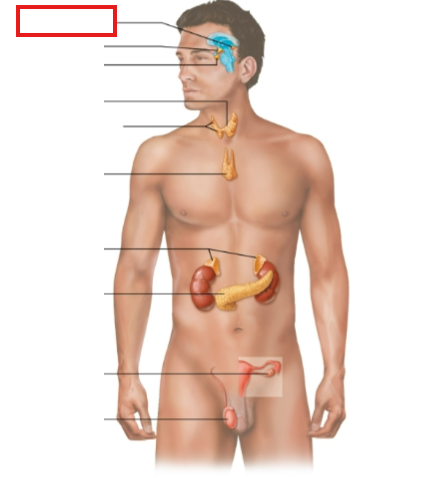

What structure is highlighted?

pineal gland

What structure is highlighted?

hypothalamus

What structure is highlighted?

pituitary gland

What structure is highlighted?

thyroid gland

What structure is highlighted?

parathyroid glands

What structure is highlighted?

thymus

What structure is highlighted?

adrenal glands

What structure is highlighted?

pancreas

What structure is highlighted?

ovary (female)

What structure is highlighted?

testes (male)